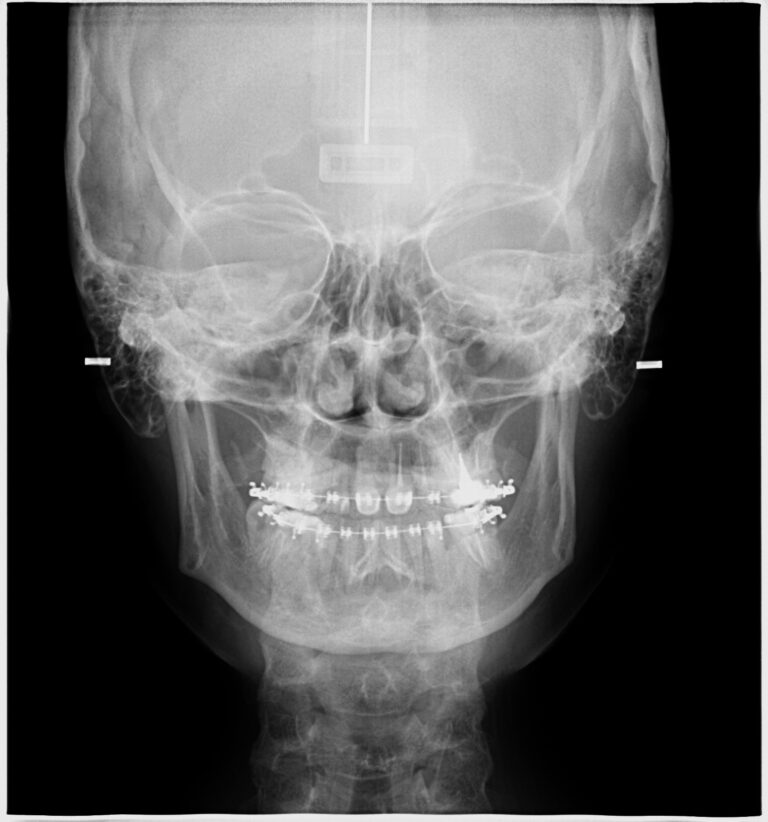

A telerradiografia frontal oferece uma visão frontal do crânio, complementando a análise lateral para um diagnóstico completo.

Avaliação da simetria facial.

Identificação de discrepâncias maxilomandibulares.

Planejamento de intervenções ortodônticas e cirúrgicas.

Análise de padrões de crescimento facial.

Imagem clara e precisa das estruturas faciais.